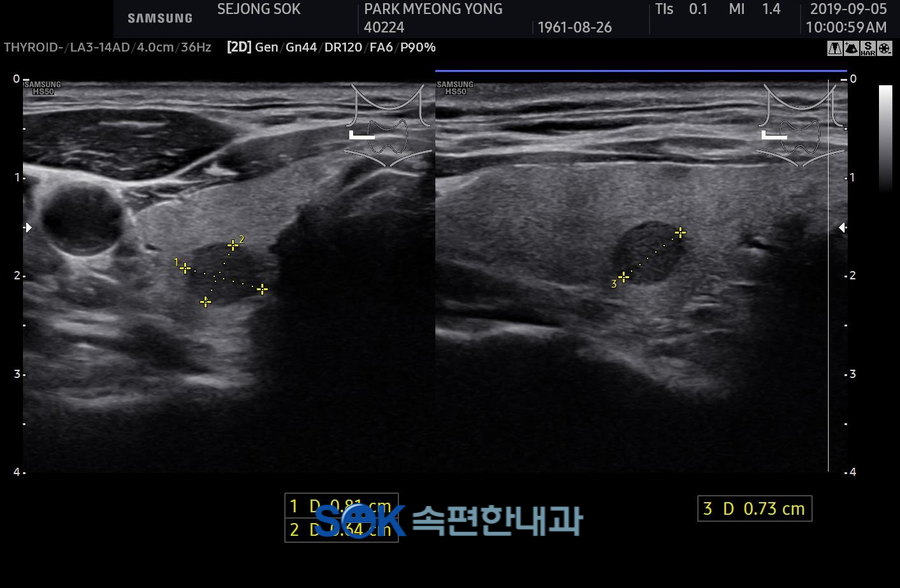

먼저 초음파 공주갑상선 검사로 설명드리면 초음파를 이용하여 갑상선의 형태와 인근 조직까지 파악하는 용도로 사용되었습니다.

이를 통해 알 수 있는 병증으로는 결절이 있지만 결절이 모두 좋지 않은 방향으로 영향을 미치는 것은 아니었어요.

2밀리미터 이내의 크기까지 확인되어도 경과를 추적하고 있으면 아무런 문제를 일으키지 않는 것을 확인할 때도 있었습니다.

이런 결절은 굳이 떼어내지 않아도 된다고 말씀드릴 수 있는데요. 실제로 40% 정도는 섬세한 결절을 가지고 있다고 생각해 주시기 바랍니다.

그 이외에 점점 커지는 경우나, 작업원 조직을 침해하는 경우는 제거하는 것을 생각할 필요가 있었습니다.

만약아까말씀드린초음파공주갑상선검사에서크고작은병변을확인했다면다음으로자세한확인이필요하다고할수있습니다.그래서 진행이 되는 게 갑상선 기능 검사였어요